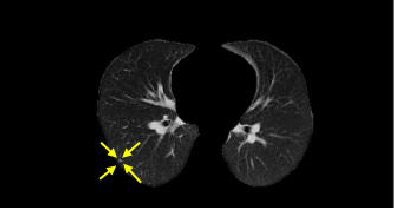

| Nodules detected by ROI detection system. Top, small nodule with inconspicuous intensity difference with surrounding lung context. Below, small well-formed nodule. Third from top, small nodule hardly distinguishable from the background and nearby thin vessels. Bottom, small irregularly shaped nodule. All images courtesy of Javad Alirezaie, Ph.D. |